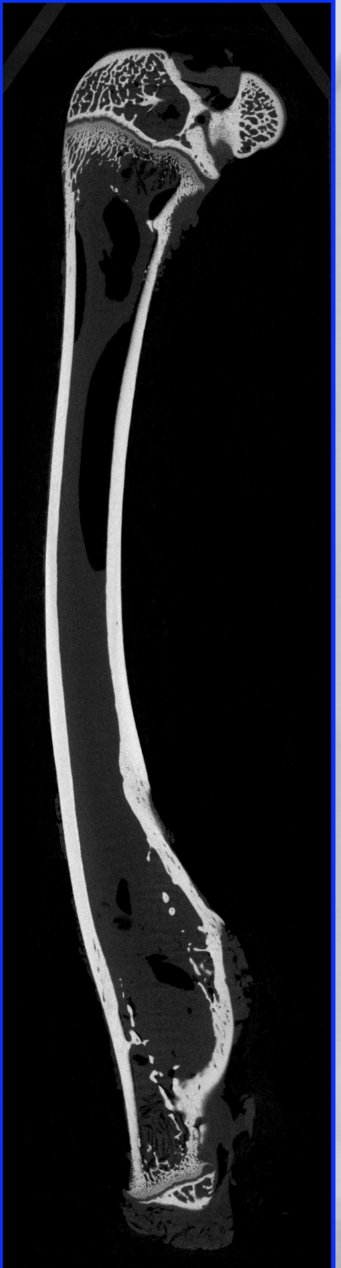

骨骼组织的三维重?nbsp;

显微 CT 可以以非破坏性的方式对骨骼组织进行三维成像,包括骨小梁的连通情况、骨密度分布等信息。这为人工骨骼的设计与制备提供了关键的参考,也可用于研究骨骼力学特性及其在仿生工程中的应用、/p>